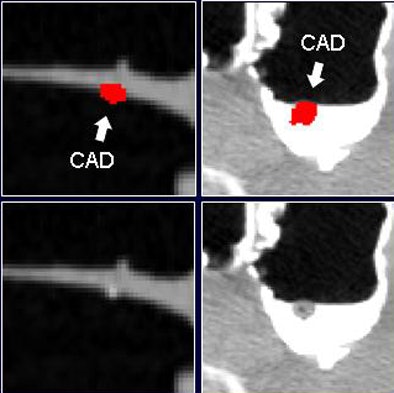

![]() |

| Before the application of the densitometric partial-volume correction and wall-connection analysis (top row) in virtual colonoscopy data, CAD misinterprets residual fecal material as polyps. These false positives are eliminated after application of the two methods (bottom row). |